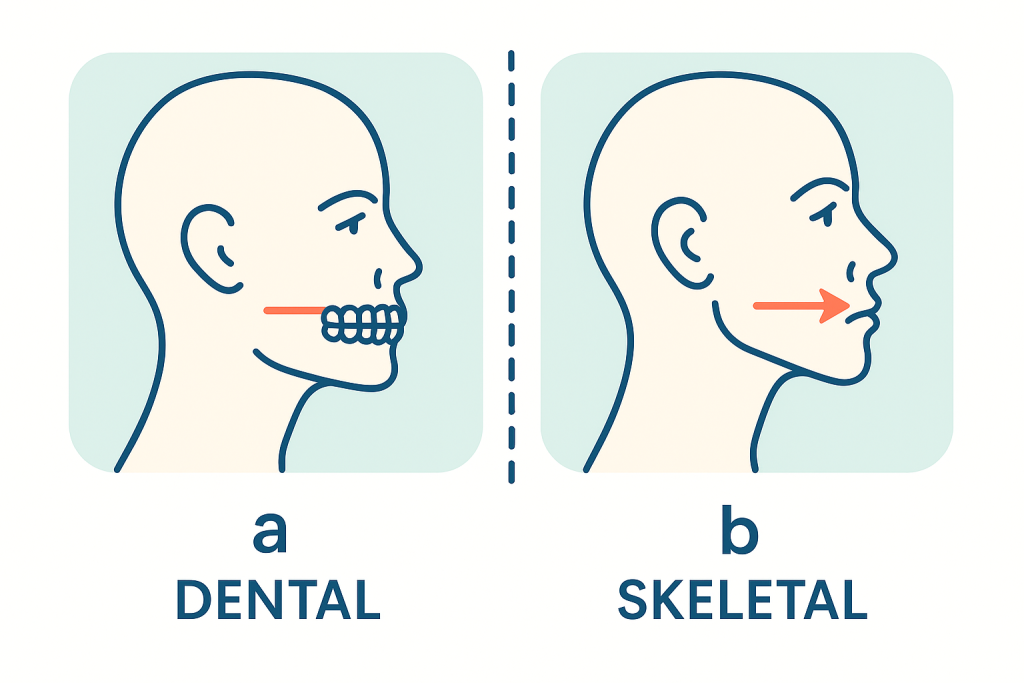

مشکلات ارتودنسی دو دستهاند:

الف) دندانی (مثل شلوغی دندانها، فاصله بین دندانها، کراسبایتهای ساده)

ب) اسکلتی (مثل جلو بودن فک بالا، عقب بودن فک پایین، رشد عمودی یا افقی صورت)

ظاهر دندانها ممکن است فقط بخش کوچک مشکل را نشان دهد، اما سفالومتری عملاً ریشه اصلی مشکل را نمایان میکند. مثلاً:

- آیا عقببودگی دندانها ناشی از عقب بودن خود فک است یا صرفاً شیب دندانها؟

- آیا جلو بودن دندانهای بالا مشکل دندانی است یا فک بالا بهطور کلی جلوتر از فک پایین قرار دارد؟

- آیا ناهماهنگی بین فکها خفیف است یا شدید؟

این تشخیص، مسیر درمان را بهطور کامل تغییر میدهد.